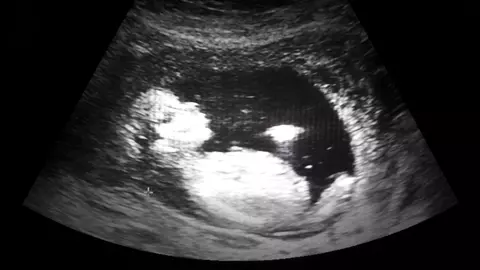

Intreruperea de sarcina, sau avortul, este procedura prin care femeia insarcinata poate opri din evolutie si elimina o sarcina nedorita, o sarcina ce ii pune viata in pericol sau care prezinta malformatii depistate prin teste de screening. Intreruperea de sarcina este o alegere dificila, in pricipal din cauza consecintelor emotionale, dar si din pricina posibilelor